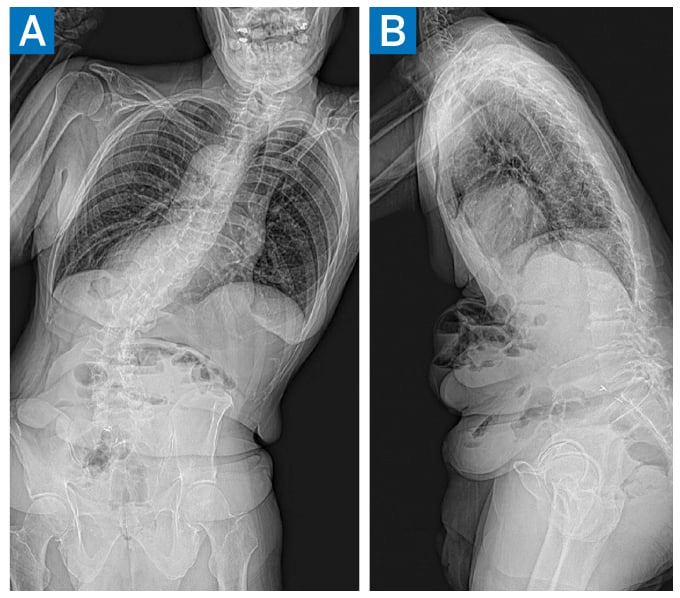

Full-length standing radiographs demonstrated coronal imbalance (CI) of 113 mm (distance from the C7 plumb line to the central sacral vertical line) and a left thoracolumbar curve of 46° (27.3° supine) (Fig. 1). Relevant pelvic parameters were T1 pelvic angle of 47°, pelvic incidence of 54°, lumbar lordosis of 12.9°(44.5° supine), and pelvic tilt of 33°. There was no leg length discrepancy. Magnetic resonance imaging (MRI) showed severe central canal stenosis at L3–L4; computed tomography (CT) scanning was notable for an average Hounsfield units of 157 (normal bone mineral density) [2].

Figure 1: Preoperative anteroposterior (AP) (A) and lateral (B) standing radiographs demonstrating multilevel spondylosis/degenerative scoliosis.